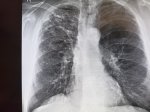

IMG20251009125406.jpg

Где пиздецома?

>>325599559

Типичный рак легких

Аноним 16/10/25 Чтв 08:58:28 #14 №325599625

>>325599617

Сфигаль?

>>325599636

Аноним 16/10/25 Чтв 09:17:43 #25 №325600106

>>325600080

пизда твоей матушки

>>325599918

Оператор лаборант же, он фоткает я описываю.

Аноним 16/10/25 Чтв 09:20:05 #27 №325600162